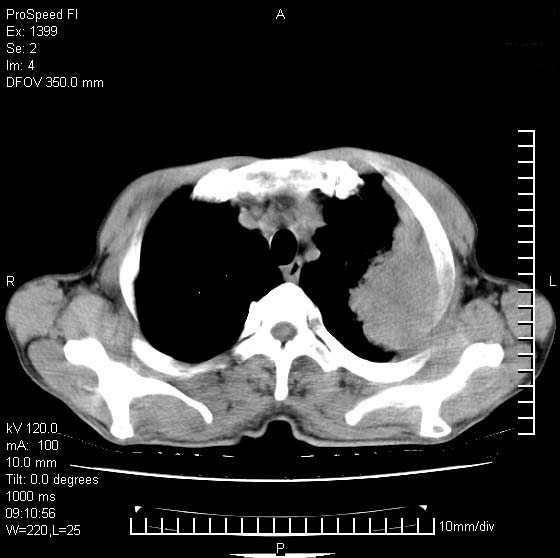

以下是引用卜一在2007-1-19 9:55:00的发言:[br]左肺沿胸膜下巨大肿块影,边缘呈分叶征,纵隔内见肿大淋巴结,右肺内另见一不规则结节影 .考虑:左肺周围性肺癌伴纵隔 右肺内转移.

以下是引用rgsyyf在2007-1-19 11:05:00的发言:[br]左肺上叶见形态不规则巨大软组织肿块影,边缘呈分叶征,纵隔内隆突下见肿大淋巴结,右肺内另见一不规则结节影 .考虑:左肺周围性肺癌伴纵隔即右肺内转移.